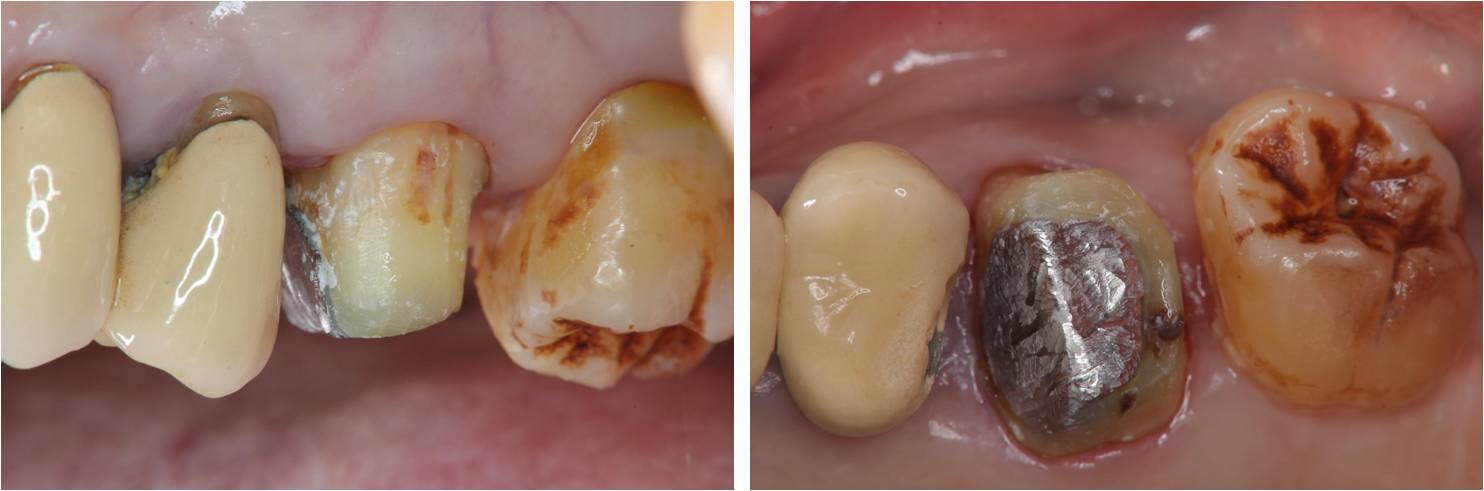

治療後口內照

治療後X光再次檢查密合性

術前、術後比較